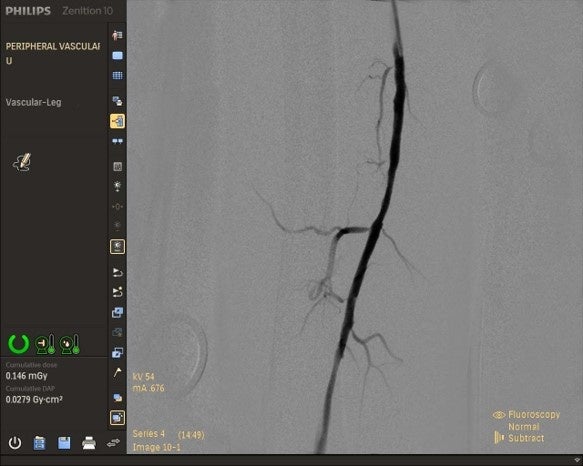

また、血管を鮮明に撮影できるため、外科だけではなく内科まで幅広く対応できます。上位機種の「Zenition 30」はもちろん、エントリーモデルの「Zenition 10」でもDSA撮影のオプション選択が可能です。

DSA機能で撮影した血管画像